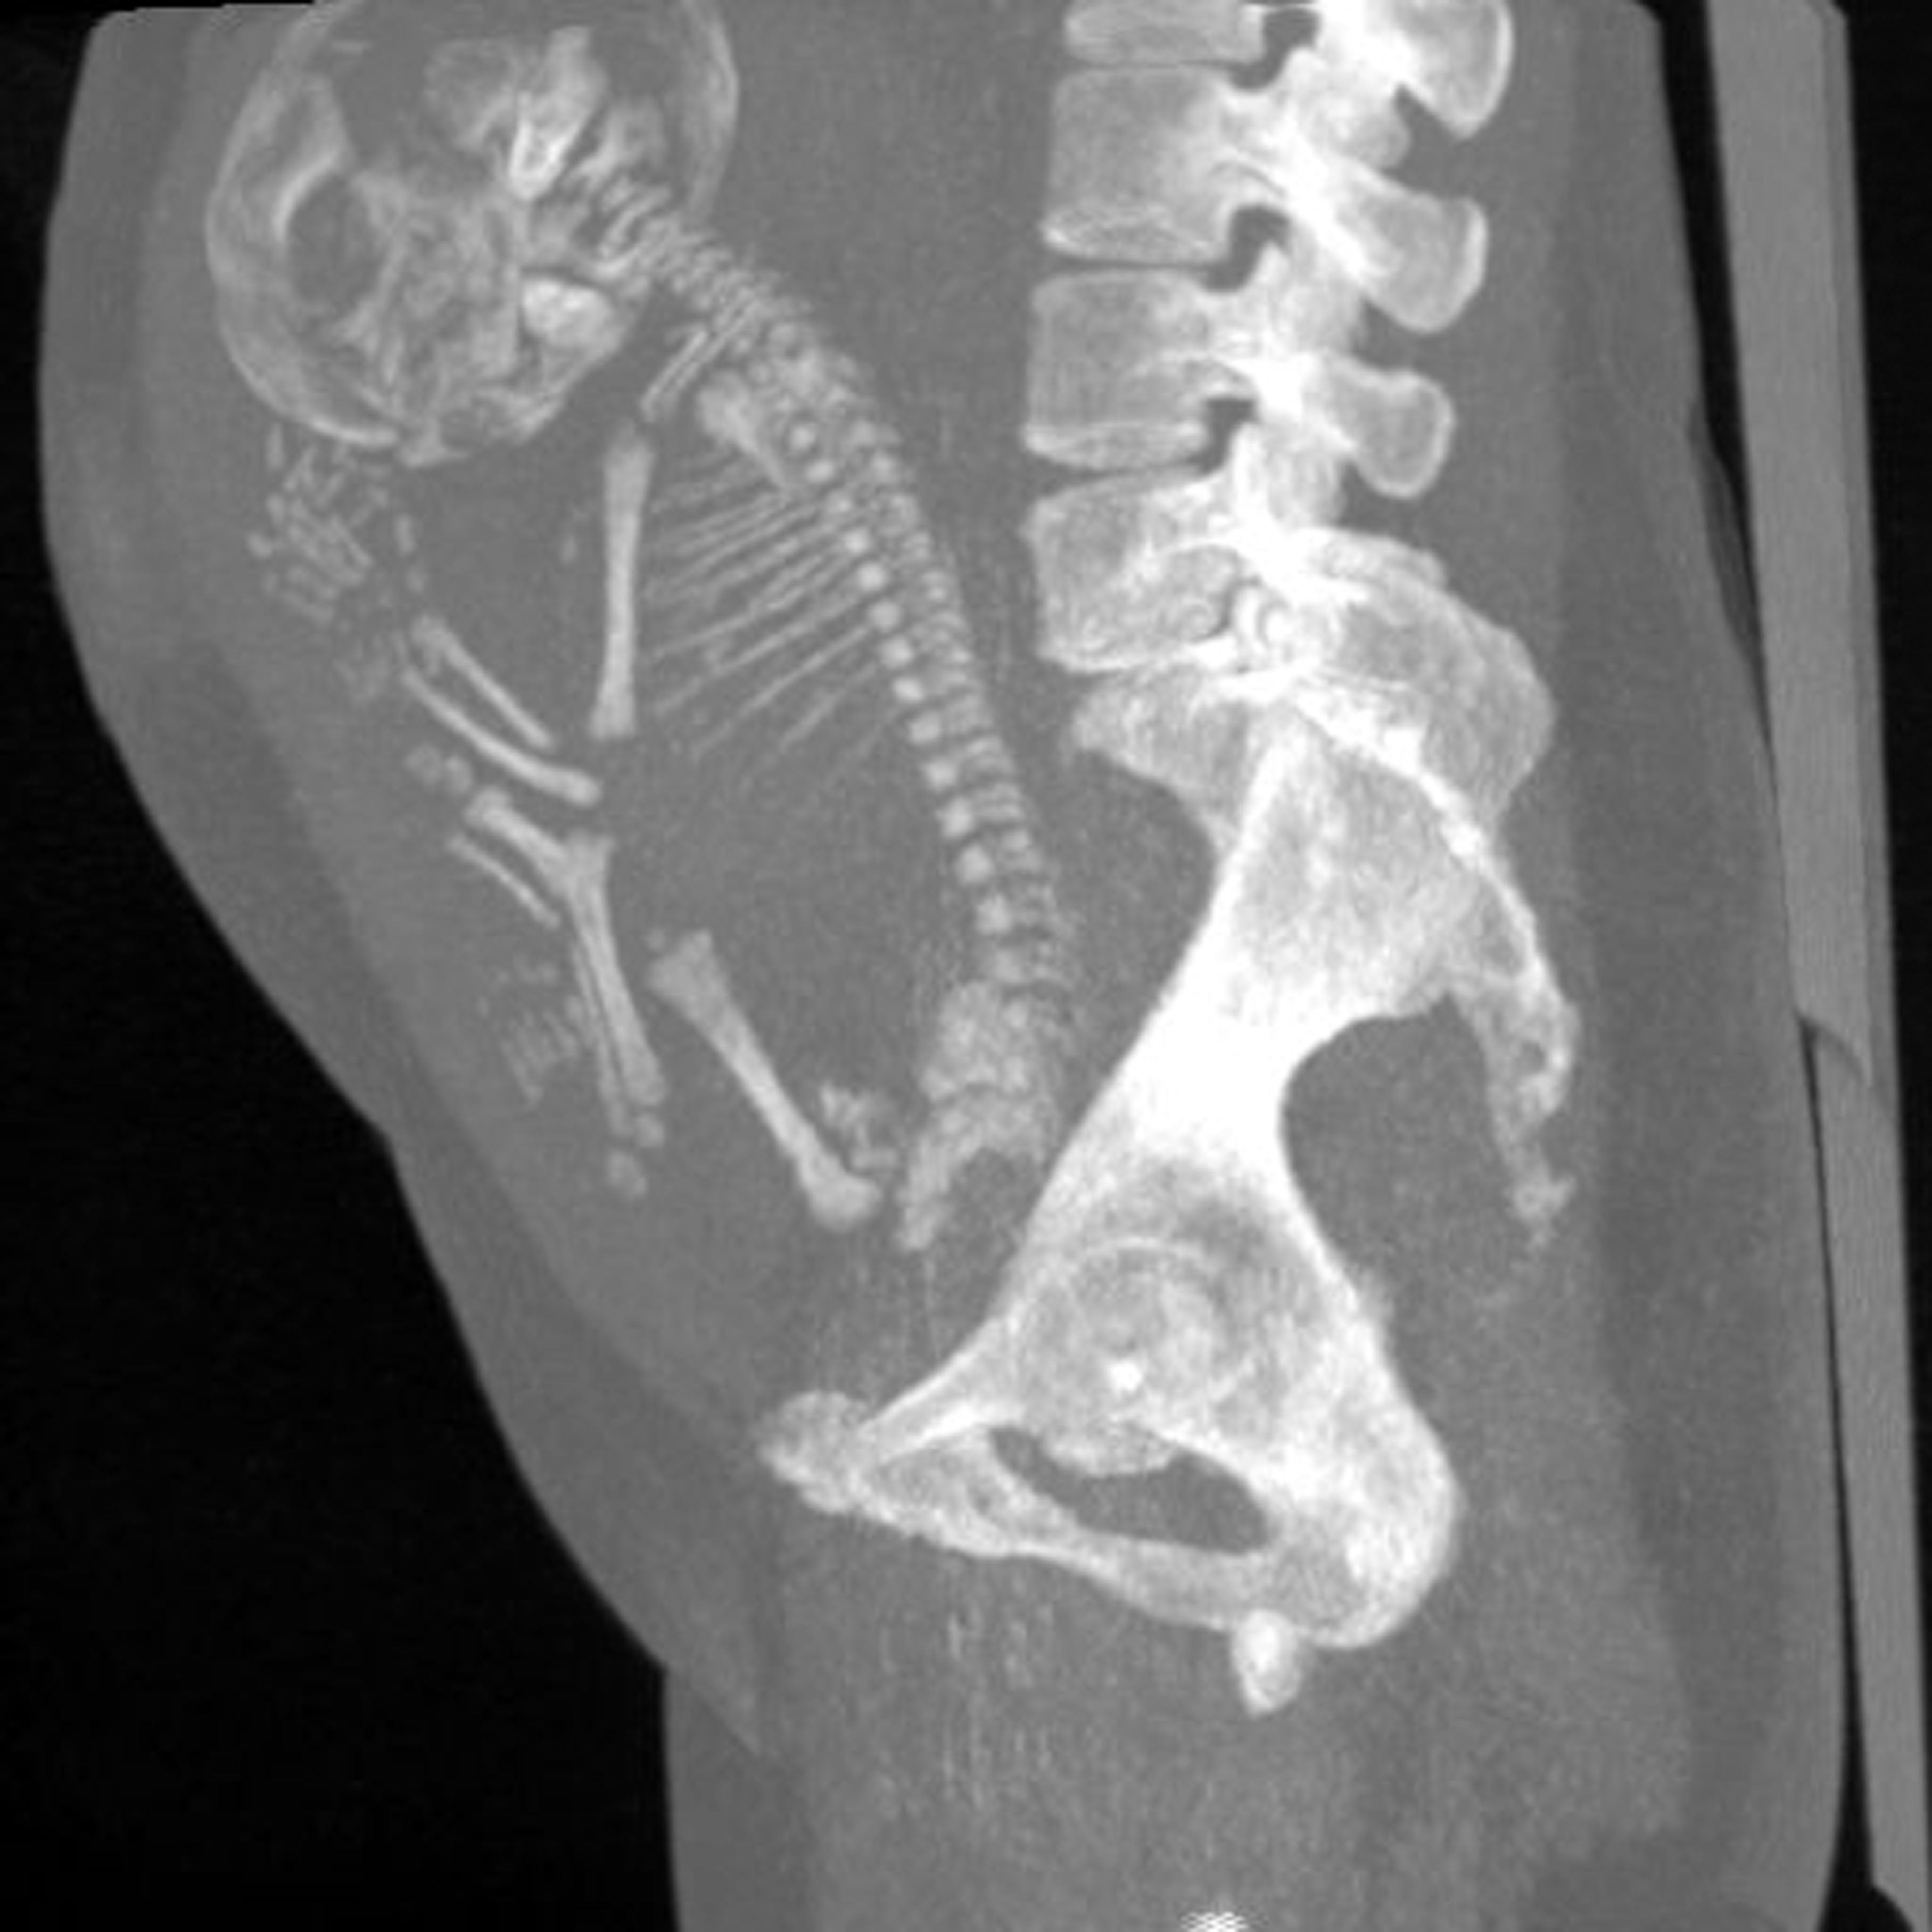

A una anciana que se quejaba de dolor de vientre se le descubrió que tenía un feto momificado en su interior, un hecho que llamó la atención de los médicos en México, donde se presentó el caso, específicamente en el estado de Durango.

La mujer, de quien no se conoce su identidad, habría estado embarazada sin darse cuenta durante 40 años, lo que generó que el feto dentro de su vientre se momificara; fue entonces cuando un dolor de estómago la obligó a asistir al médico, donde los expertos en salud confirmaron la presencia del feto.

En cuanto a la explicación científica de este inusual hecho, los médicos creen que el feto se calcificó, en un raro evento llamado lithopaedion, que es extraordinariamente raro, en el que el exterior del cuerpo del feto se calcifica como parte del intento del cuerpo de la madre de protegerse.

Es así como parte de una reacción a un cuerpo extraño para proteger a la madre del tejido muerto y de contraer una infección. Los médicos calculan que el bebé murió y fue momificado en la semana 40 del embarazo después de no desarrollarse normalmente, según el Daily Star.

Los informes afirman que es poco probable que la madre recibiera atención prenatal adecuada cuando el bebé fue concebido hace unos 40 años. Su situación es tan rara que solo se han registrado unos 300 casos de litopedia.

Según Public Med Central, este inusual caso médico se puede describir como un embarazo ectópico abdominal en el que el feto muere, pero no puede ser reabsorbido por el cuerpo de la madre. El feto muerto queda retenido en la cavidad abdominal, formando una capa de calcio a su alrededor.

El litopedion se ha descrito en mujeres con edades comprendidas entre 23 y 100 años, siendo dos tercios de ellas mayores de 40 años. El período de retención del feto fue de 4 a 60 años. En este caso, se desconoce el período de retención exacto, pero es razonable pensar que podría ser al menos 40 años.